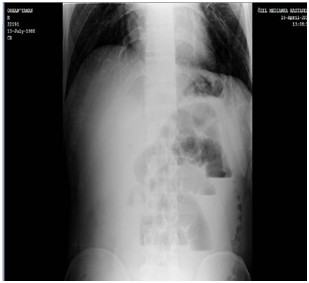

A 28 years-old male presented to the general surgery clinic with a one-week history of intermittent abdominal pain, nausea and distention. He had a history of multiple admissions to different hospitals with similar symptoms during this period. On physical examination, diffuse abdominal tenderness, distension and increased bowel sounds on auscultation were found. Abdominal ultrasound was unremarkable. A plain abdominal X-ray revealed distended small bowel loops and air-fluid levels which indicated ileus. (Figure 1) On laboratory blood tests, WBC was 16.3 x 10(9)/L and C-reactive protein was 119mg/L. Obstructive ileus was considered as a diagnosis and surgical intervention was performed to explore the underlying cause for intestinal obstruction. On exploratory laparotomy, a large ileo-cecal intussusception was found with moderate swelling of the ileum. A right hemicolectomy and an ileo-colic anastomosis were performed.

Figure 1 Plain abdominal X-Ray Distended small bowel loops and air-fluid levels.